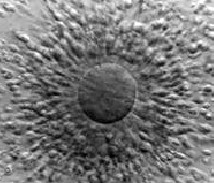

Ziua recoltarii ovulelor

Sperma este recoltata prin procedura IFV sau ICSI.

Un numar de celule incojoara ovulul care in prealabil a fost aspirat dintr-un

folicul matur.